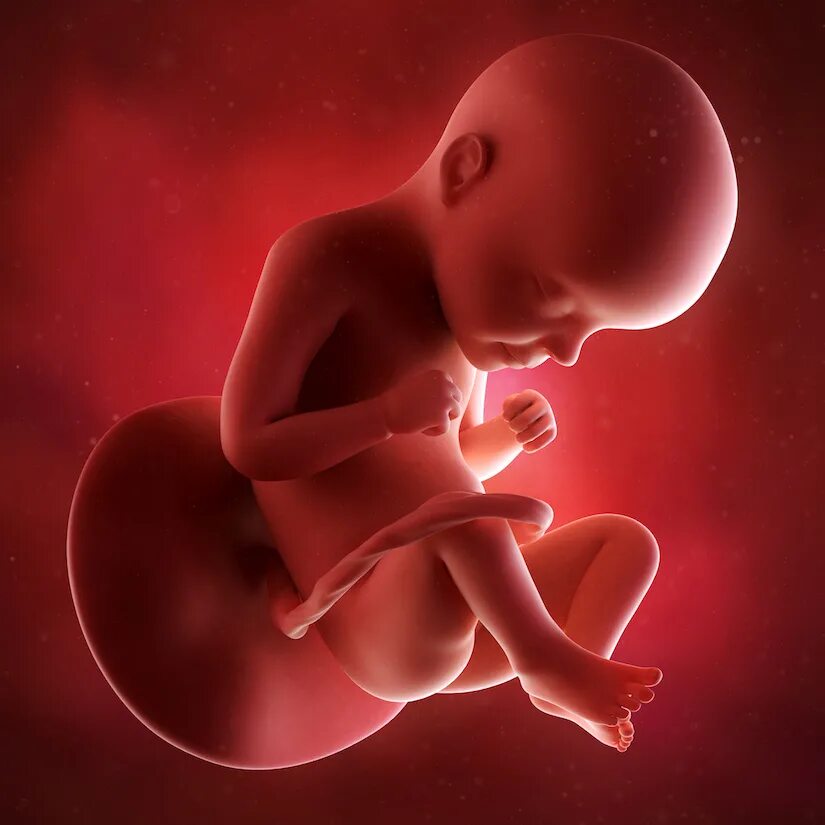

Ребенок в утробе 31 неделя